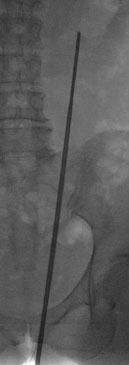

![]() |

| Starres Endoskop in der Niere | Starres Endoskop in der Niere |